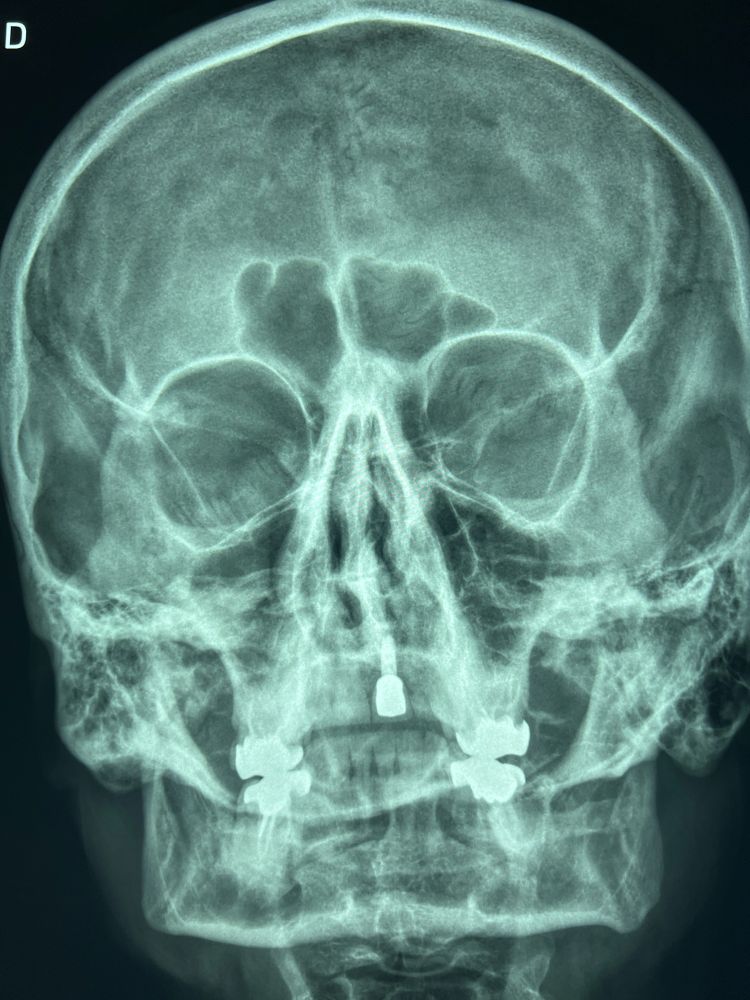

C'est pire de face, le telecanthus est encore plus flagrant